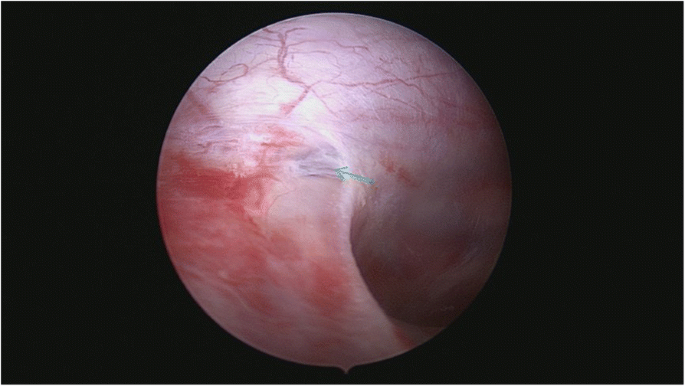

After general anesthesia and endotracheal intubation, the patient was placed in prone position. A fluoroscopy was used to determine the correct operative level, and a longitudinal incision was made 5 cm off midline at the T12 level. Muscle was dissected layer by layer, and a spinal process and left lamina were exposed. The left lamina was partially ground by cutting burr and then removed along with ligamentum flavum by Kerrison punch. After that, the cyst was exposed. Under a microscope, the cystic wall was fenestrated and it then drained off clear cystic fluid (cerebral spinal fluid). After partial excision of the cyst and evacuation of cystic fluid, a spinal endoscope (SPINENDOS, Germany) was maneuvered into the space and the fistula was detected (Figs. 6, 7). The fistula was detached from the arachnoid membrane and was ligated with a 7–0 Vicryl purse string suture. Regional leakage from the repaired site was noted. An anastoclip was then used to close the fistula (Fig. 8). Pulmonary pressure was elevated by ventilator (valsalva maneuver) to check the leakage and there was no more leakage. Hemostatic matrix and gel [Fibrin sealant kit (human), (Shanghai RAAS Blood Products Co, Ltd., Shanghai, China)] were utilized at the local region. The postoperative diagnosis was a thoracolumbar extradural arachnoid cyst. The pathological report revealed an arachnoid cyst (Fig. 9). The symptoms improved on postoperative day 2. His lower limbs regained strength with limited dorsiflexion of the right foot.